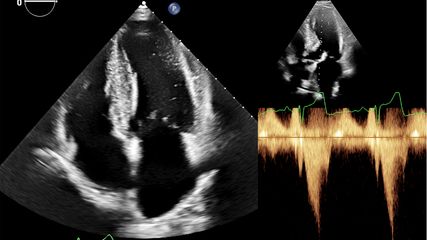

3. Schwerpunkt – Bildgebung

Die primäre Methode zur Beurteilung der Koronararterien bei Patient:innen mit ACS ist weiterhin die invasive Koronarangiografie. Diese ermöglicht es, zugrunde liegende Koronarveränderungen zu diagnostizieren und die erforderlichen therapeutischen Maßnahmen unverzüglich zu ergreifen. Eine initiale notfallmäßige transthorakale Echokardiografie (TTE) wird bei Patient:innen mit Verdacht auf ACS und kardiogenem Schock empfohlen (I-C), welche bei diagnostischer Unsicherheit jedoch nicht zu einer Verzögerung des Transfers ins Herzkatheterlabor führen soll (IIa-C). Die routinemäßige Koronar-Computertomografie-Angiografie („coronary computed tomography angiography“; CCTA) bei Verdacht auf ACS mit inkonklusivem EKG und hs-cTn wurde in den neuen Leitlinien herabgestuft, kann aber weiterhin in Betracht gezogen werden (IIa-A). Bei Patient:innen mit Verdacht auf einen akuten Koronarverschluss, bei denen eine Notfall-Angiografie Vorrang hat, ist die CCTA nicht sinnvoll (III-B).

Intravaskuläre Bildgebung soll zur Unterstützung und Optimierung der PCI bei ACS-Patient:innen überlegt werden (IIa-A). Eine Metaanalyse der verfügbaren kleinen randomisierten Studien auf diesem Gebiet zeigt die Überlegenheit der PCI mit intravaskulärem Ultraschall (IVUS) in der Verringerung von MACE.7 Insbesondere die optische Kohärenztomografie („optical coherence tomography“; OCT) kann bei Patient:innen mit unklarer und/oder fehlender schuldiger Läsion zur Planung der weiteren Vorgehensweise herangezogen werden (IIb-C).